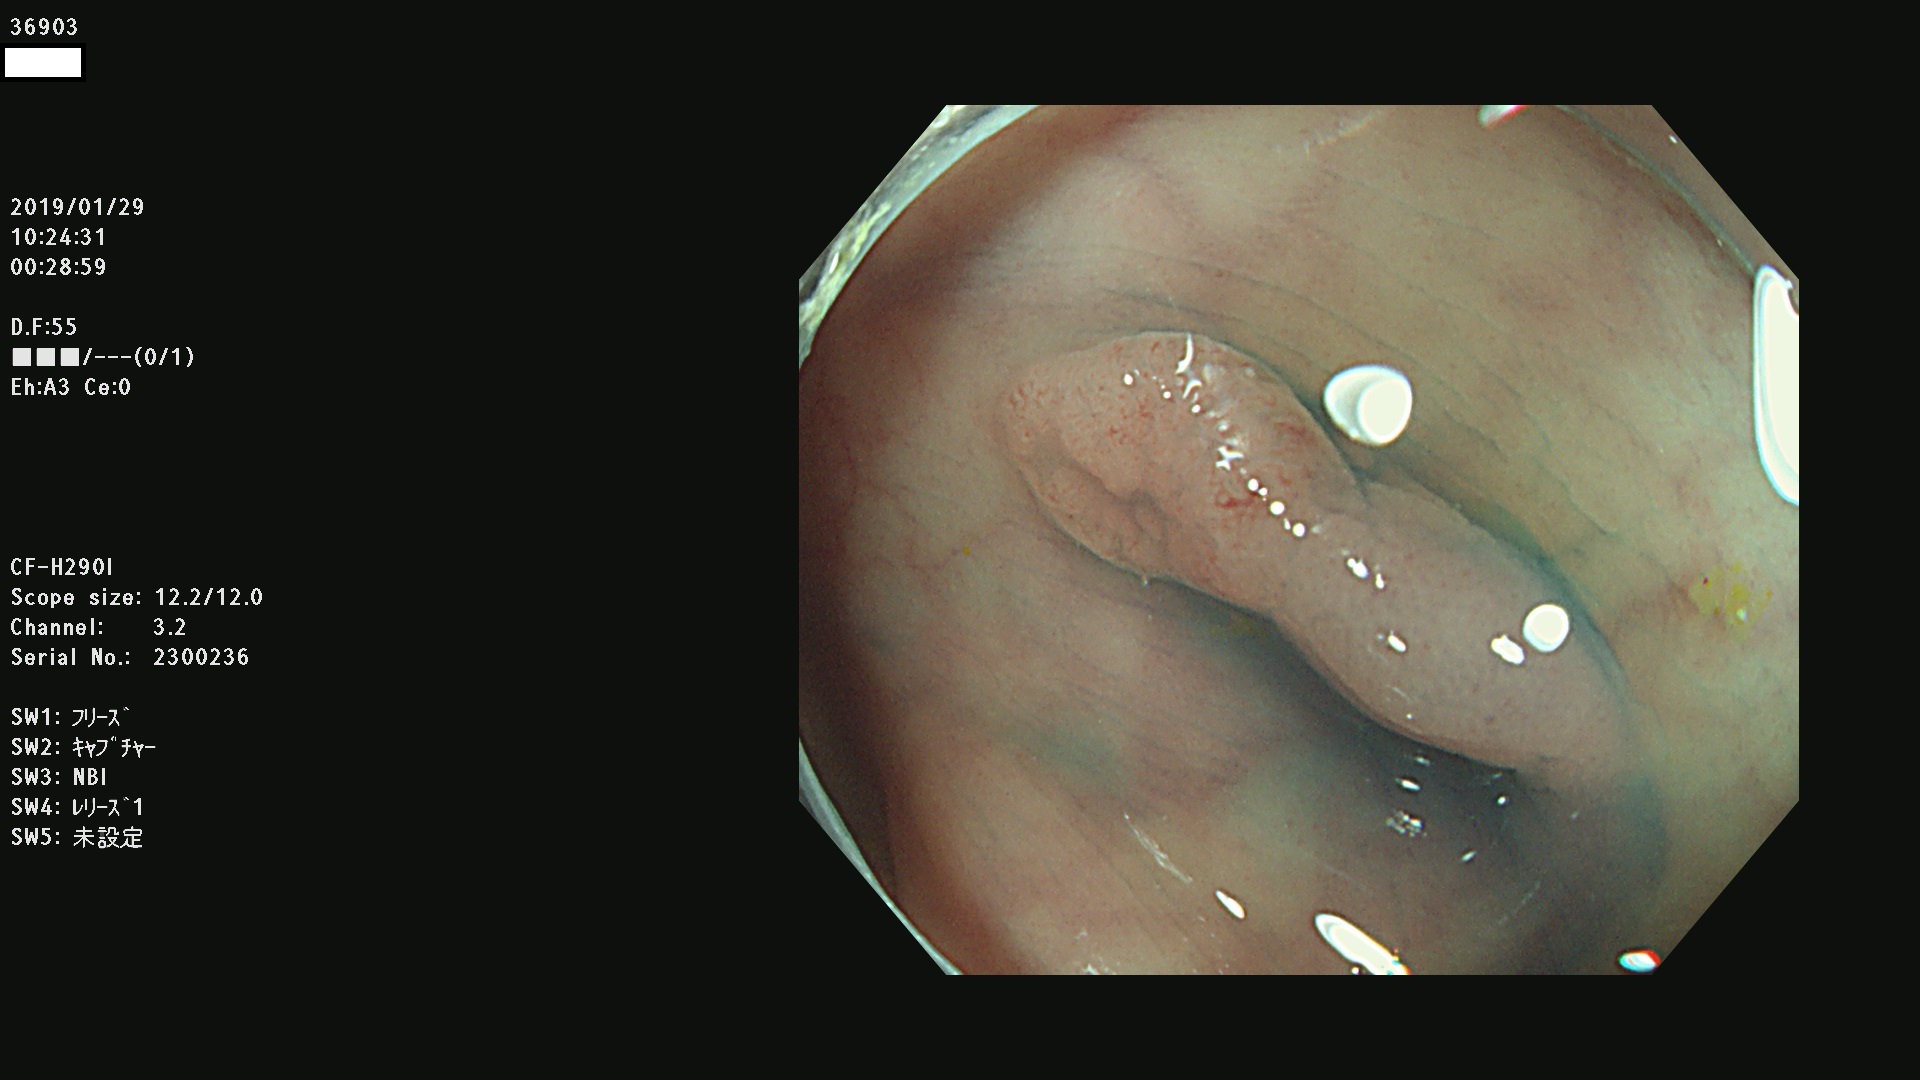

腺腫発見率 67 % (カルテ番号 36900〜36999の100名の方の検査結果で集計)大腸癌検診最新情報

以下のカルテ番号の方に腺腫(Adenoma,Group3〜5)が見つかりました(集計法)

36900 36901 36903 36904 36905 36908 36909 36910 36911 36913 36914 36915 36916 36917 36918 36919 36920 36923 36924 36925 36927 36928 36930 36931(SSAPのみ) 36933 36935 36936 36937 36941 36943 36944 36945 36946 36949 36951 36953 36954 36955 36957 36963 36965 36966 36967 36968 36969 36970 36974 36975 36976 36977 36978 36979 36980 36981 36983 36984 36986 36987 36988 36989 36990 36991 36993 36994 36996 36998 36999

発見困難で危険性の高い平坦型病変(上記100名より抽出) ![]()